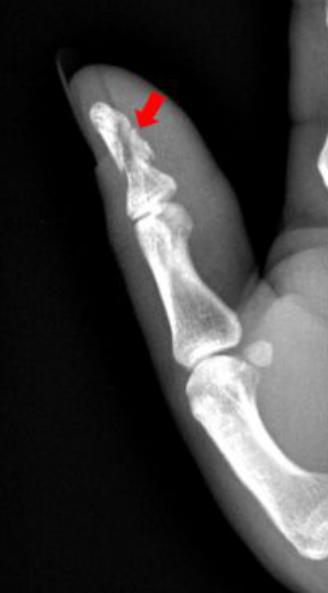

1、患者拇指被车门挤压,拍片如下:

右手拇指远节指骨甲粗隆游离骨碎片影